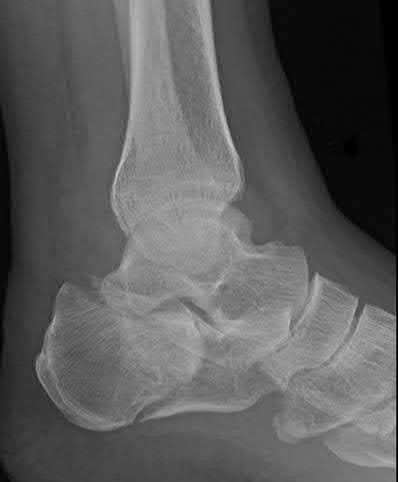

A 25-year-old male sustains an ankle fracture dislocation and undergoes open reduction and internal fixation. He returns to clinic five months following surgery complaining of continued ankle pain and instability with weight bearing. His immediate post-operative AP radiograph is seen in Figure A. Which of the following could have prevented this patient from developing persistent pain?

The patient presents with continued ankle pain and instability following open reduction and internal fixation. The radiograph in figure A demonstrates inadequate restoration of fibular length, likely leading to continued tibiotalar instability.

Illustration A demonstrates fibular malreduction with dislocation of the fibula anterior to the tibial incisura. Illustration B shows a comminuted fibula fracture along with a measurement of length from an intact fibula. The arc from the lateral process of the talus to the peroneal groove of the distal fibula is known as the "dime" sign and should remain unbroken if fibular length has been restored. Illustration C demonstrates the use of a push-pull screw and lamina spreader to regain length intraoperatively for a comminuted fibula fracture.